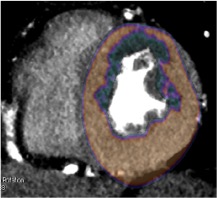

STUDIO DI PERFUSIONE (FASE FUNZIONALE POST-STRESS FARMACOLOGICO)

L’immagine mostra un chiaro deficit di perfusione, transmurale, in corrispondenza della parete anteriore del ventricolo sinistro (asse corto ventricolare sinistro, regionale verde scura) nel contesto del miocardio normoperfuso (regioni arancione). Tale deficit è da scriversi alla stenosi identificata sull’arteria discendente anteriore in fase anatomica.